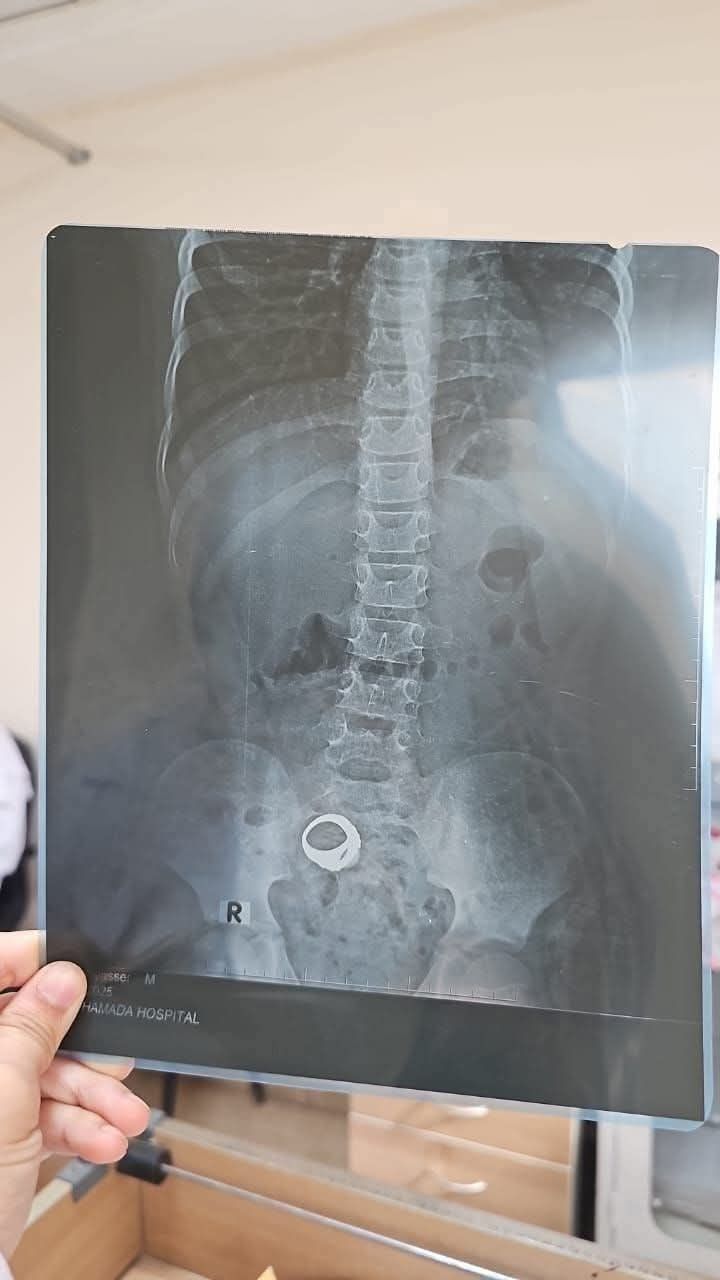

الخاتم المعندى يظهر فى الأشعة

وأصدرت إدارة مستشفى كوم حمادة العام بيانًا إعلاميًا عبر صفحتها على موقع فيس بوك بشأن حالة الطفل معاذ عمار، الذي دخل المستشفى مساء أمس الخميس، وكان يعاني من تلبك معوي نتيجة وجود خاتم معدني داخل بطنه.